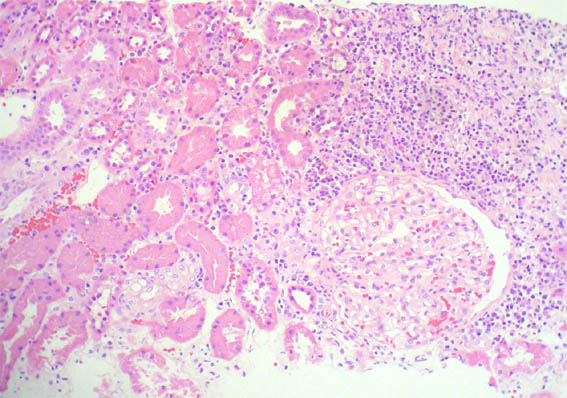

An allograft kidney biopsy was done. See the images.

Figure 1. H&E, X100.